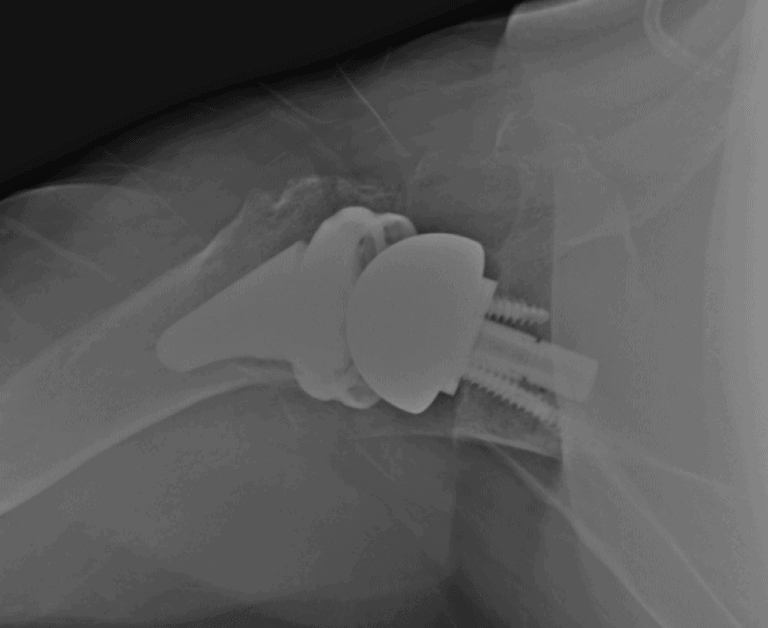

Arthrex, Apex

Selected